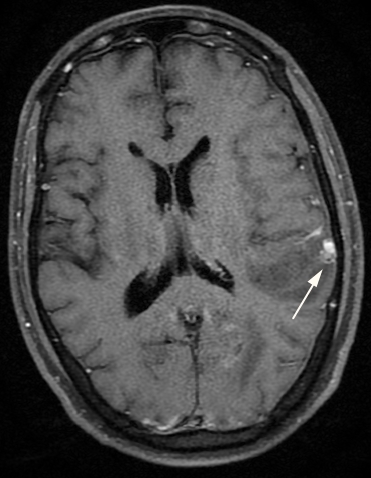

Enhancing peripheral dura-based nodule in left parietal region likely to be Granulomatous nodule / Granulomatous angitis was also reported (Figure 2).

Figure 2: Contrast MR Images Showing Left Parietal Dura Based Enhancing Nodule (Arrow)

Pachymeningeal involvement is more frequent than leptomeninges. The frequency of Hypertrophic Pachymeningitis (HP) in adult AAV ranges from 18 to 35% [12]. HP typically shows linear thickening of dura mater or a bulging mass with enhancement on brain MRI and computed tomography scan [13]. Enhancing peripheral dura-based nodule in our case represents HP.